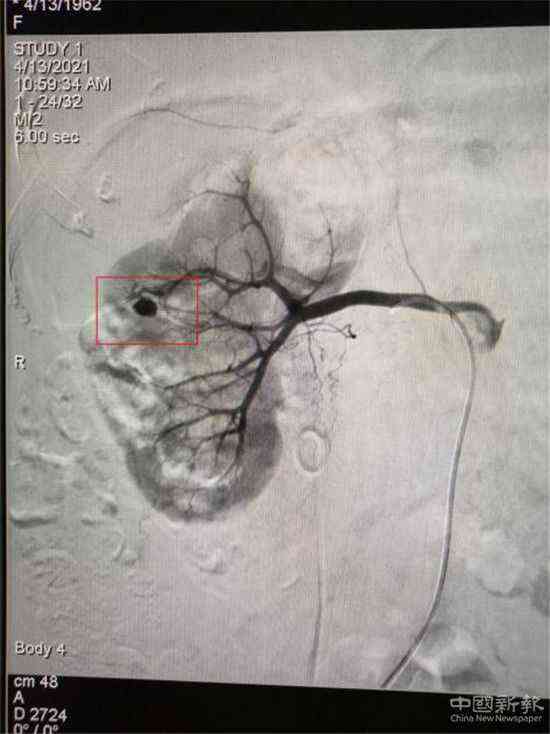

栓塞前造影圖(紅圈標(biāo)記為出血處)

家住湖南省郴州市嘉禾縣廣發(fā)鎮(zhèn)的鄧大媽,因患巨大腎結(jié)石進(jìn)行了“經(jīng)皮腎鏡取石術(shù)”,術(shù)后第3天出現(xiàn)大量鮮紅色血尿。經(jīng)過(guò)增強(qiáng)CT檢查,考慮為“腎穿刺口處動(dòng)脈出血”,醫(yī)院介入血管外科團(tuán)隊(duì)立即為患者在DSA下行“微創(chuàng)介入右腎出血?jiǎng)用}栓塞術(shù)”,術(shù)后出血立刻停止,尿液由紅色轉(zhuǎn)為正常顏色。